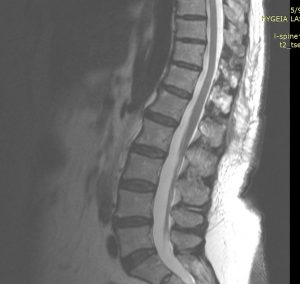

Η μετεγχειρητική πορεία ήταν ανεπίπλεκτη με άμεση βελτίωση τόσο του πόνου όσο και της μυικής ισχύος και βάδισης της ασθενούς. Ο μετεγχειρητικός έλεγχος 3μήνου με μαγνητική τομογραφία αναδεικνύει την ολική εξαίρεση του μηνιγγιώματος αλλά και το εξαιρετικά περιορισμένο χειρουργικό τραύμα, λόγω της πεταλοπλαστικής.

Ο λόγος που επέλεξα να παρουσιάσω το περιστατικό αυτό δεν είναι το μηνιγγίωμα της κατώτερης θωρακικής μοίρας ή το γεγονός ότι επετεύχθη ολική εξαίρεση. Αυτό στο οποίο θέλω να εστιάσω είναι η προσπέλαση και συγκεκριμένα η τεχνική της πεταλοτομίας-πεταλοπλαστικής. Σε αντίθεση με την πεταλεκτομία, όπου τα οπίσθια στοιχεία (δηλ. ένα τμήμα της “ραχοκοκκαλιάς”) αφαιρούνται μόνιμα, στην πεταλοπλαστική τα πέταλα επανατοποθετούνται και οι σύνδεσμοι συρράφονται, επιτυγχάνοντας έτσι την αποκατάσταση της ανατομίας της σπονδυλικής στήλης. Αυτό έχει πολλαπλά οφέλη: δεν επηρεάζεται η σταθερότητα της σπονδυλικής στήλης, δε δημιουργείται ουλή πάνω στη μήνιγγα, μειώνεται σημαντικά το ποσοστό διαφυγής εγκεφαλονωτιαίου υγρού κ.α.